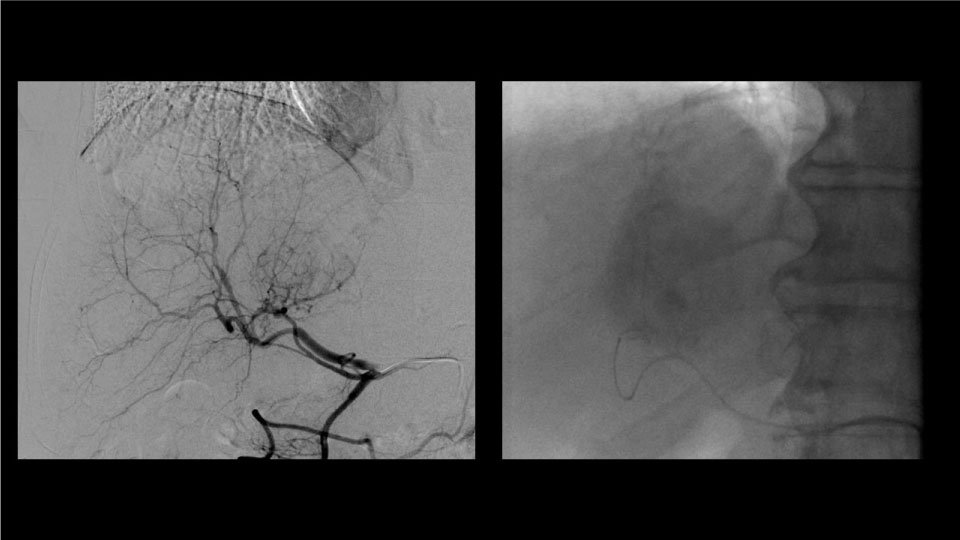

L’oncologie interventionnelle est un ensemble d’intervention qui vise à détruire complètement ou diminuer la taille d’une tumeur

Ces interventions sont toujours proposées après concertation multidisciplinaire, où toutes options thérapeutiques sont envisagées